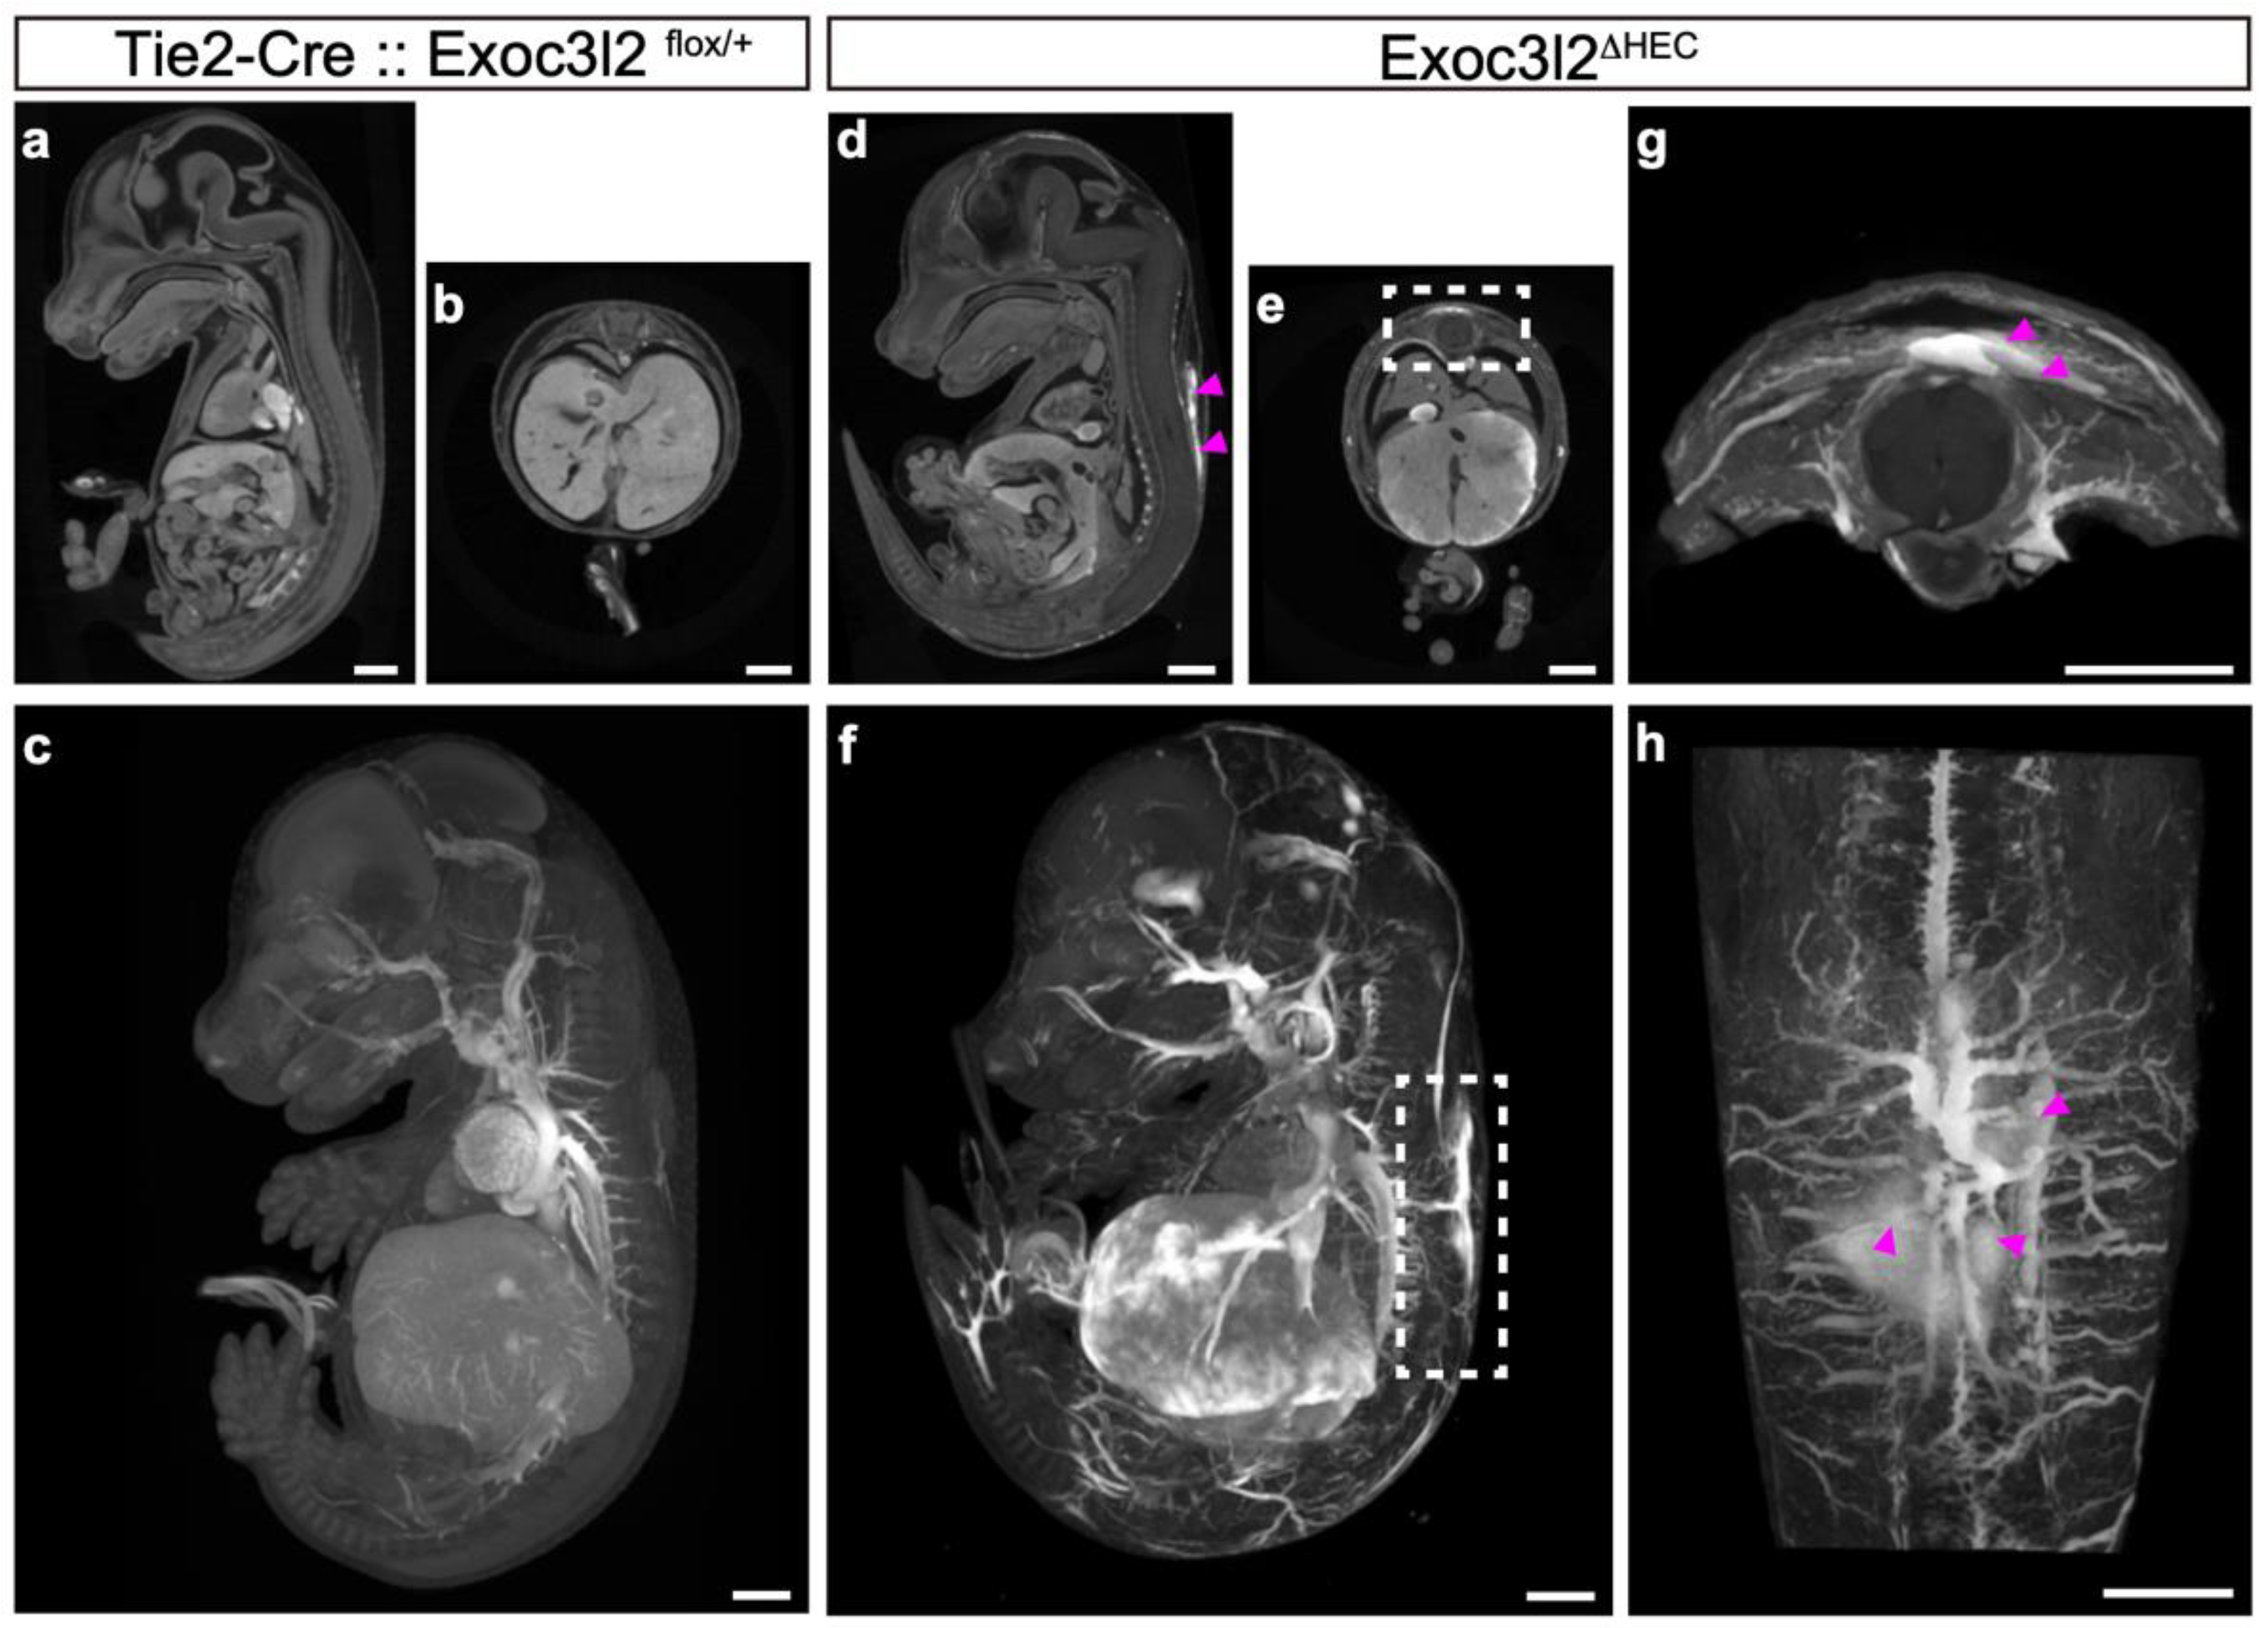

3.3. Phenotypes of Tie2-Cre: Exoc3l2 Conditional Knock-Out Embryos